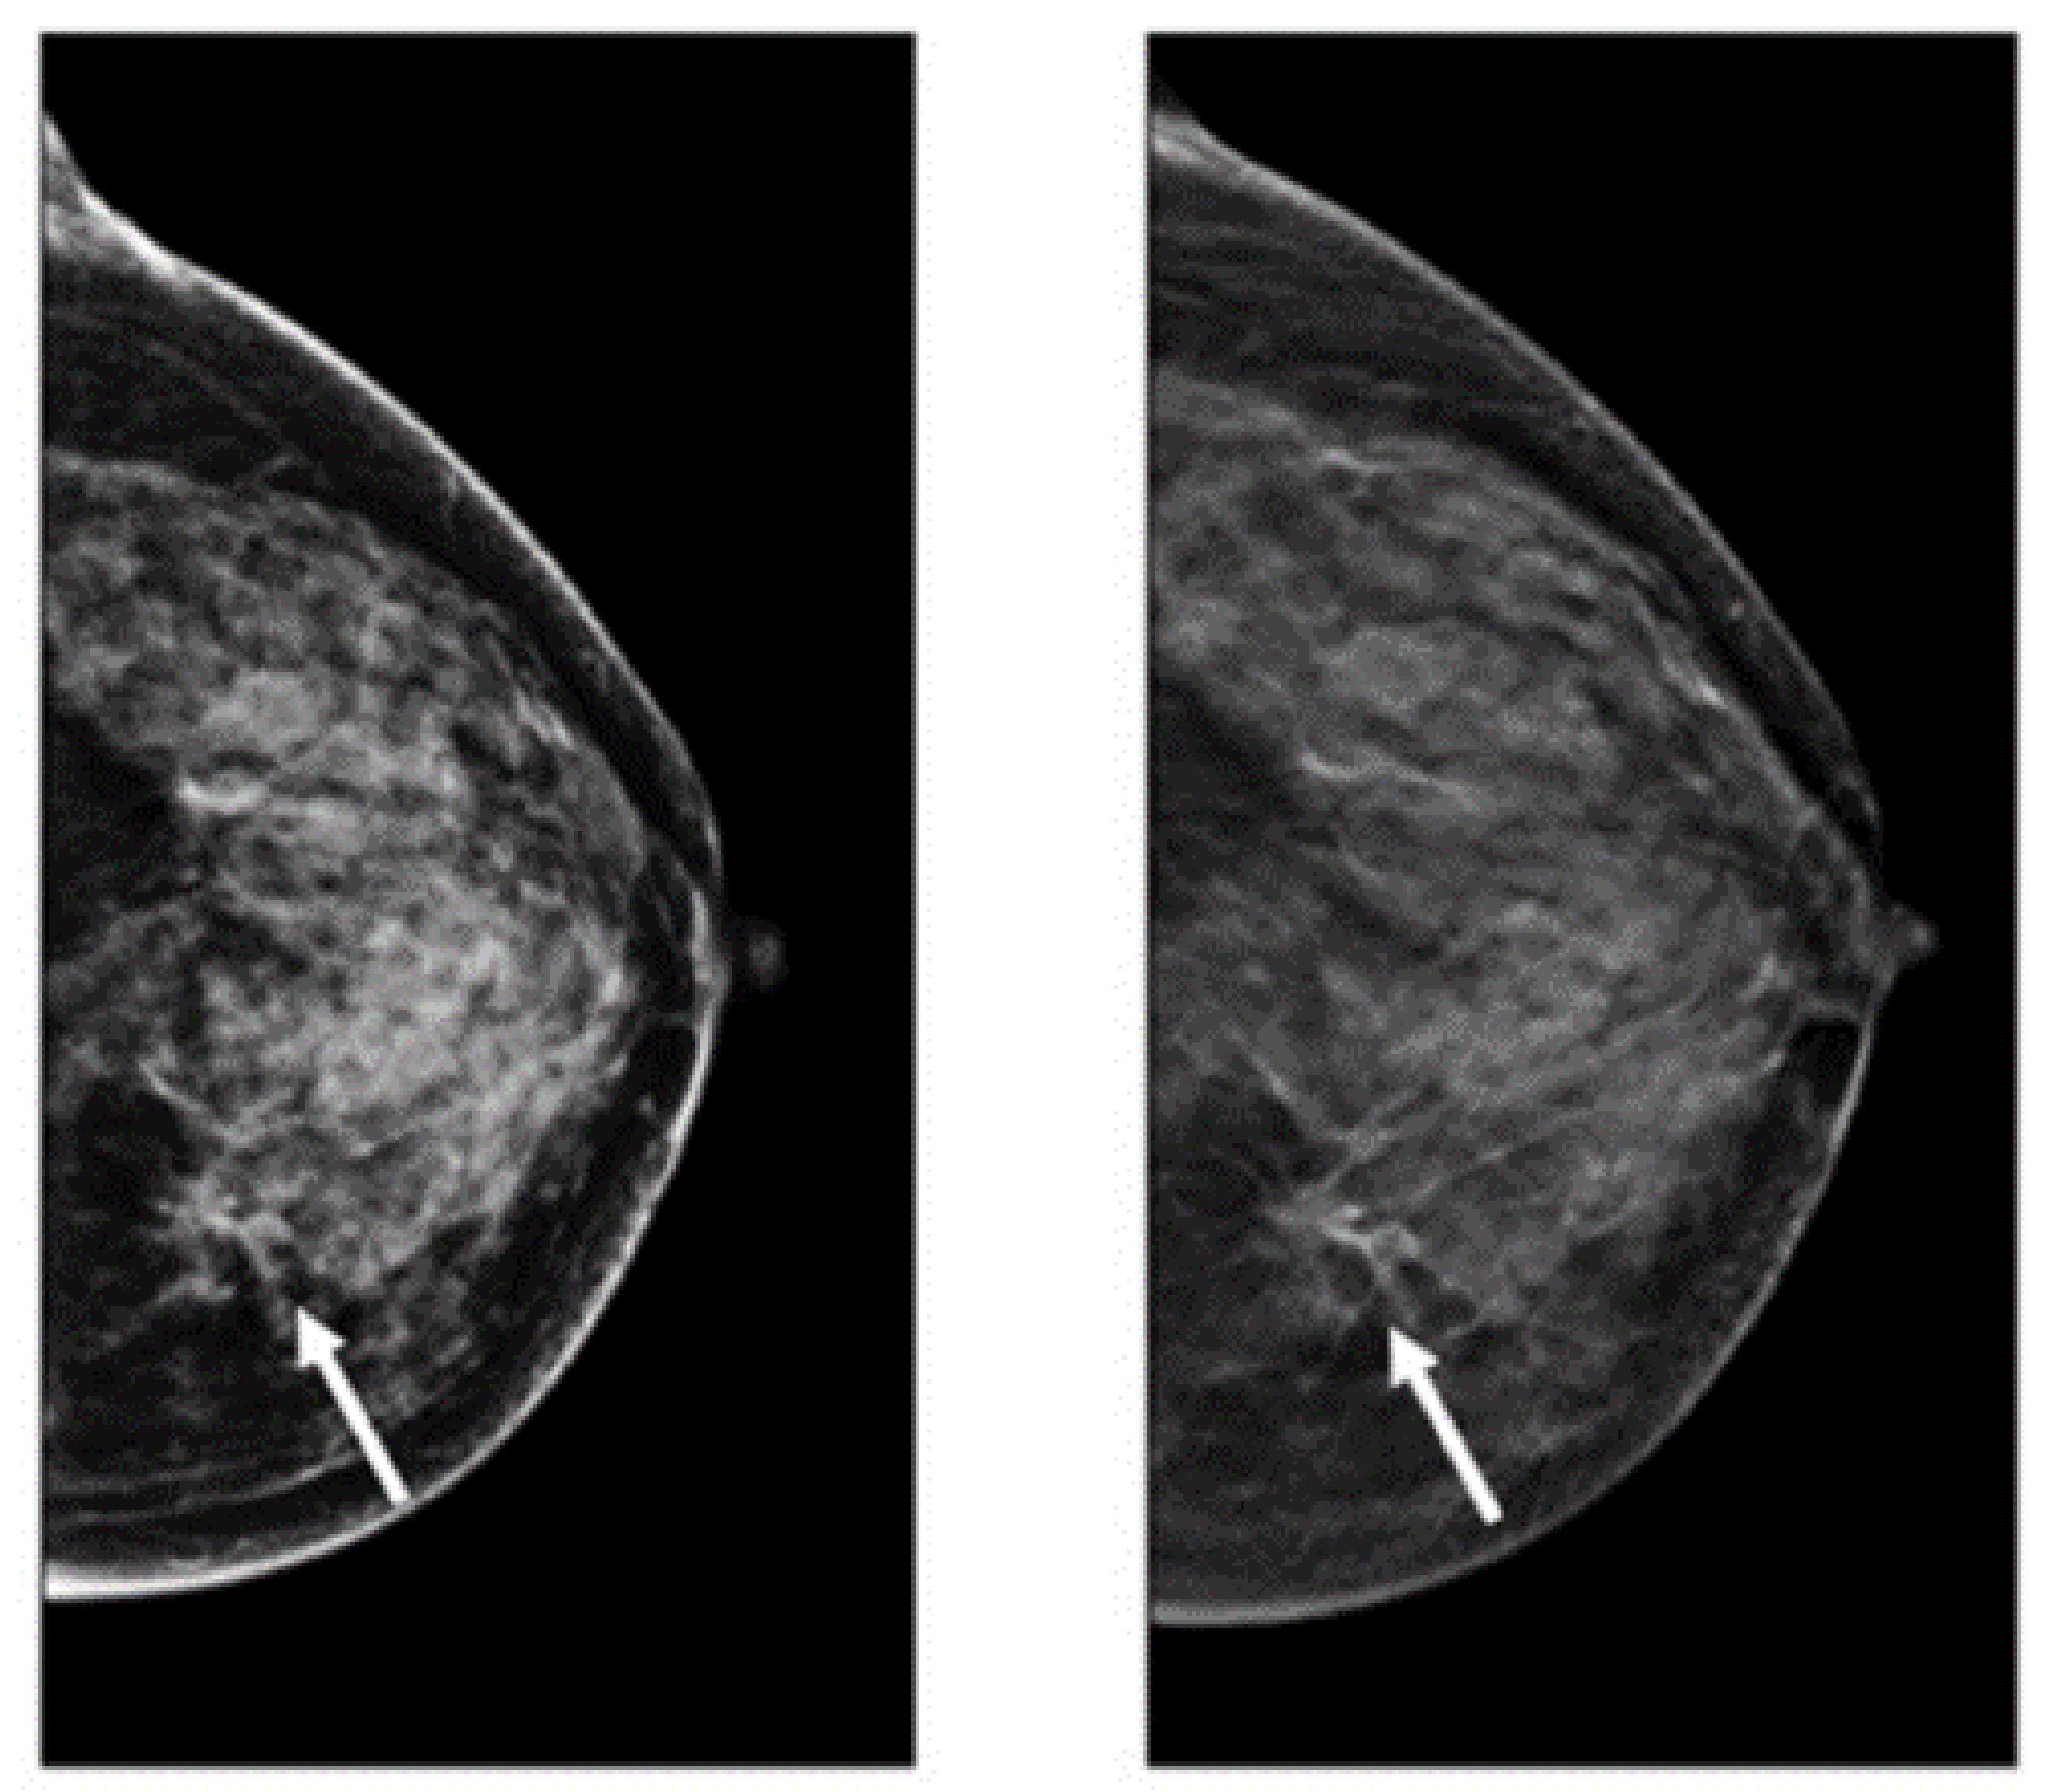

DBT is a novel imaging modality making 3D images of breasts by the utilization of X-rays captured from different angles [50]. This method is similar to what is performed in mammograms, except the tube with the X-ray moves in a circular arc around the breast [51,52,53] (Figure 2). Repeated exposures to the breast tissue at different angles produce DBT images in half-millimeter slices. In this method, computational methods are utilized to collect information received from X-ray images to produce z-stack breast images and 2D reconstruction images [53,54]. In contrast to the conventional FSM method, DBT can easily cover the imaging of tumors from small to large size, especially in the case of small lesions and dense breasts [55]. However, the main challenging issue regarding the DBT is the long reading time because of the number of mammograms, the z-stack of images, and the number of recall rates for architectural distortion type of breast cancer abnormality [56]. After FFDM, DBT is the commonly used method for imaging modalities. Many studies recently used this imaging modality for breast cancer detection due to its favorable sensitivity and accuracy in screening and producing better details of tissue in breast cancer [57,58,59,60]. Table 1 provides details of the pros and cons of DBT for breast cancer analysis.

Figure 2.

Images of cancerous breast tissue by DBT imaging modality [61]. Reprinted/adapted with permission from [61]. 2021, Elsevier.